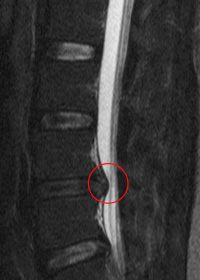

椎間板ヘルニア

年齢による変化、スポーツなどによる負荷がきっかけで、椎間板(ついかんばん)の中身がとびだして神経根(しんけいこん)や脊髄(せきずい)を圧迫し、腰の痛みや足のしびれを引き起こします。手術が必要なこともありますが、軽度の場合は姿勢や動作に気をつければ自然に治ることもあります。